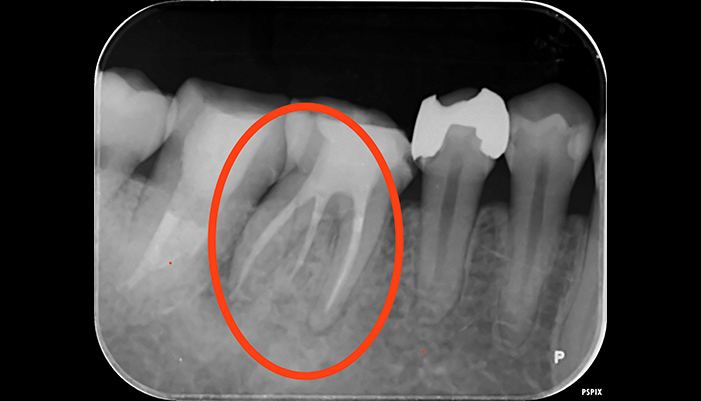

治療前

治療後

| 主訴 | 虫歯がある。根の管が細すぎて見当たらない。 |

|---|---|

| 治療期間 | 1回 |

| 費用 | 再根管治療132,000円(税込)+ ファイバーコア44,000円(税込)= 176,000円(税込) |

| 治療内容 | ラバーダムを用いて無菌的な環境下で根管治療を行いました。 マイクロスコープ下で虫歯を完全に取り切り、根の管の細さが0.06mm程度になっていたため慎重にNiTiファイルを用いて根管形成を行い、 薬液や超音波器具による洗浄、体に馴染みの良い材質による充填、被せ物を支え、再感染しないように土台を立てました。 |